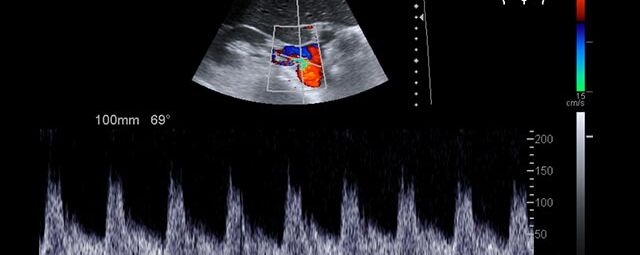

Die Sonographie ist ein bildgebendes Verfahren in der medizinischen Diagnostik, das mit Ultraschallwellen arbeitet. Ultraschall ist Schall mit einer Frequenz oberhalb der menschlichen Hörgrenze. Im medizinischen Bereich werden je nach Körperregion Ultraschallwellen in einem Frequenzbereich von ca. 3,5 – 18 Mhz verwendet. Die körpernahe Ultraschallsonde sendet durch einen piezoelektrischen Effekt kurze Schallwellenimpulse in den Körper. Ultraschall-Gel stellt den Kontakt zwischen Sonde und Körper her. Je nach Gewebeart werden diese Schallwellen im Körper unterschiedlich stark reflektiert. Anhand des zurückgesendeten Schallmusters kann das Ultraschallgerät Schnittbilder berechnen, auf denen die Organe des Körpers nach krankhaften Veränderungen untersucht werden können.